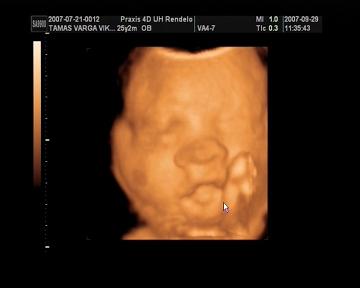

Megjöttünk az uh-ról. Jelentem óriásbébivel rendelkezem! Néhány adat a sok-sok közül: BPD: 8,84 cm AC:29,1 cm FL: 5,94 cm. Becsült súly: 2057 g. Mért adatok alapján becsült terhességi hét: 33.hét 5. nap. :) Úgyhogy Bendő két héttel előrébb jár kb. Viszont hosszban nem olyan hosszú, 40 cm körül van.

Azt mondta a doki bácsi, hogy teljesen egészségesnek tűnik és nagyon szép. Teszek fel képet!

Viki! Tényleg nagyon szép a kissrác! A második képen olyan, mintha magában mulatna valamin :wink: És a méretei nem semmik :shock: Látom, a Praxisban voltatok. Nagyon megbízhatóan, megnyugtatóan át szokták nézni a babákat, nem csak moziznak, és ez jó szerintem.

Varga Viki:Nagyon édes a kisfiad, a második képen mintha elmosolyodott volna.Mi szerdán voltunk ultrahangon a 32.héten járunk akkor volt 2130g és 42cm és azt mondt a doki, hogy átlagos baba, de szerintem óriás bébi lesz.Szedtél valami vitamint?

Meddig tartott a vizsgálat?Mi is voltunk a 30.héten fantasztikus élmény volt.